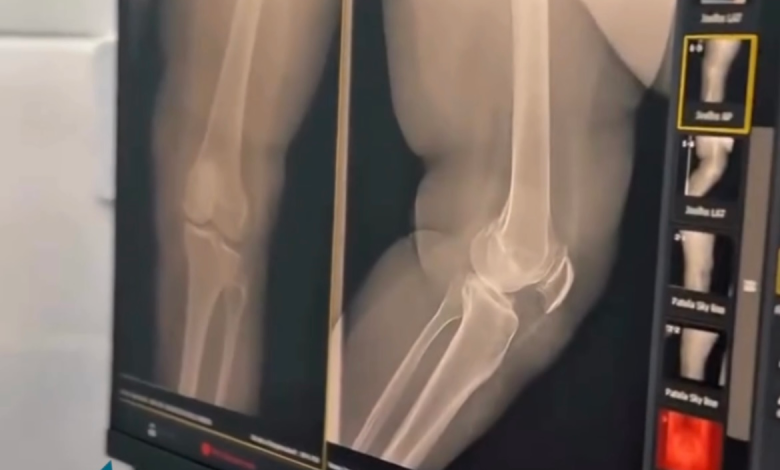

Um marco importante para a saúde de Porto da Folha foi celebrado nesta quinta-feira com a reinauguração da Sala de Raio-X do Hospital de Pequeno Porte. O espaço, totalmente adequado e equipado para melhor atender a população, representa mais um passo na consolidação de uma gestão voltada ao cuidado e ao fortalecimento do sistema de saúde municipal.